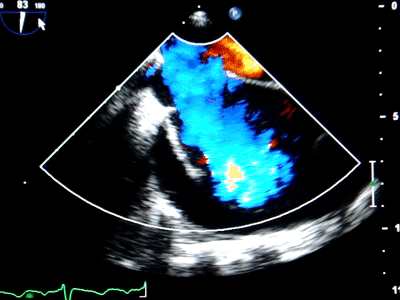

潍坊市第二人民医院超声医学科自2019年开展经食管超声心动图检

市中心医院超声医学科成功完成经食管超声心动图检查 据了解,经食管

而"经食管超声心动图监测技"将超声探头经口腔放置于食道和胃底,能够